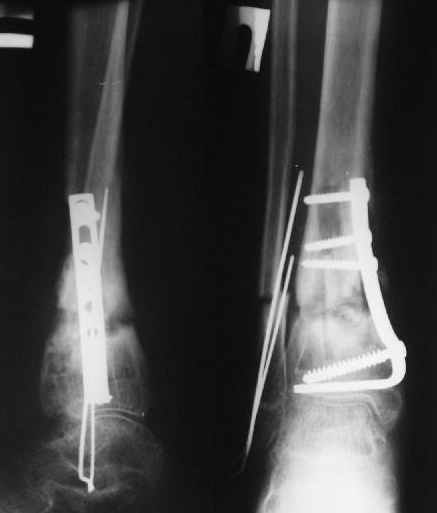

Уважаемые коллеги!Поступила пациентка 40лет, псевдоартроз Н/3 большеберцовой кости, оперирована 1,5-а года назад по поводу перелома ПИЛОНА в Австрии, травма горнолыжная.

после остеосиннтеза |  05.07.04 |  12.04.05 | Пластина удалена через 4-е месяца (миграция винтов), полимерная повязка на 2-а мес. Беспокоит деформация голени,укорочение 1-1,5см, боли незначительные, движения в г/стопном суставе в полном объёме, ходит с полной нагрузкой на ногу, подвижность в переломе не определяется. Одномоментное исправление деформации, костная пластика (chronOS)+ пластина? Аппаратная коррекция, затем пластина? Аппарат? Прошу Ваших советов. С Уважением А.Миронов